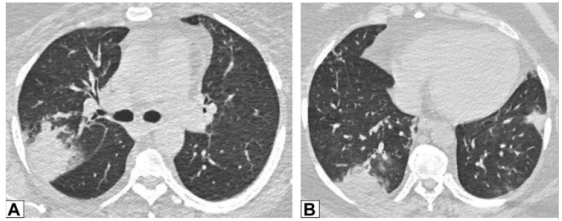

图源:Chest, 2022, 162(1):156-178.图3A为71岁男性,2011年7月因劳力性呼吸困难就诊,胸片显示右肺上叶实变。图3B为2012年6月再次检查显示右肺上叶异常已消失,左肺出现广泛实变。图3C为2013年6月,左肺病变消失,但右肺下叶出现新的实变。这些发现是典型的OP游走性表现。图源:Chest, 2022, 162(1):156-178.图3所示患者胸部CT可见磨玻璃影伴小叶间隔增厚和铺路石征的游走灶(图4)。由此可见,OP的实变可以发生在肺的任何部位,边界清晰或模糊,呈游走性特点。图源:Chest, 2022, 162(1):156-178.OP的实变可以呈局灶性、多发性和弥漫性,也可以表现为结节或肿块。图5所示患者为70岁女性,COVID-19确诊9个月后出现持续气促,CT平扫图像显示支气管血管周围多灶性肿块样实变。在类固醇治疗后症状显著改善,实变消退,推测诊断为OP。图源:Chest, 2022, 162(1):156-178.实变常伴支气管充气征,可伴散在的磨玻璃样低密度或小实质结节。以主要的或完全的磨玻璃低密度为表现者较少见。图6A所示为一名有甲状腺乳头状癌病史的47岁男性患者碘131治疗4个月后的CT平扫图像,可见右肺上叶支气管血管周围磨玻璃影。PET/CT扫描显示磨玻璃影代谢增高(图6B)。CT平扫图像显示左肺上叶新出现的磨玻璃影(图6C)。支气管活检结果与OP相符。图源:Chest, 2022, 162(1):156-178.图7为一名71岁男性患者因使用胺碘酮导致SOP的CT平扫图像,可见左肺广泛磨玻璃影,小叶间隔增厚(铺路石征)。磨玻璃低密度影合并小叶间隔增厚可表现为铺路征。